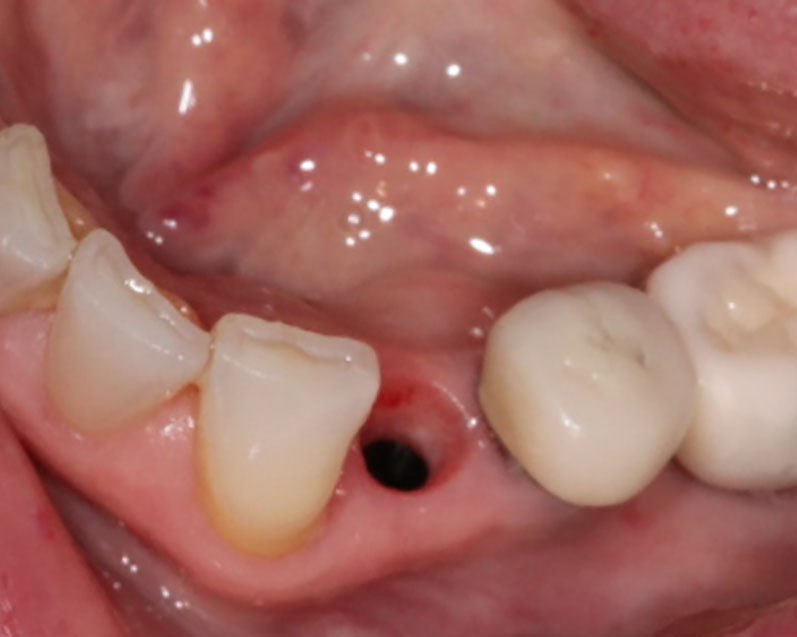

Implants

This treatment involves implanting artificial dental roots, and restoring dental crown without damaging the adjacent teeth.